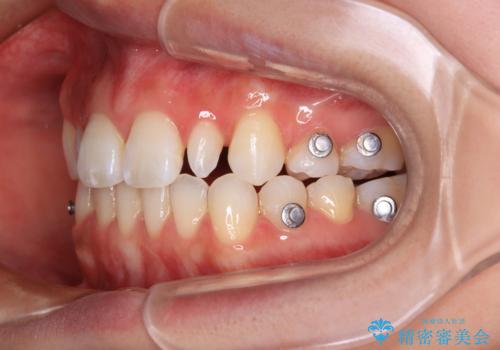

- 矯正装置

- インビザライン

遠方の地元へ転居する予定があるとのことで、インビザラインによる治療を希望されていらっしゃいました。

治療途中で地元へ転居され、飛行機での通院となったため、治療期間が長くなりましたが、自然で整った口元に仕上げることができました。